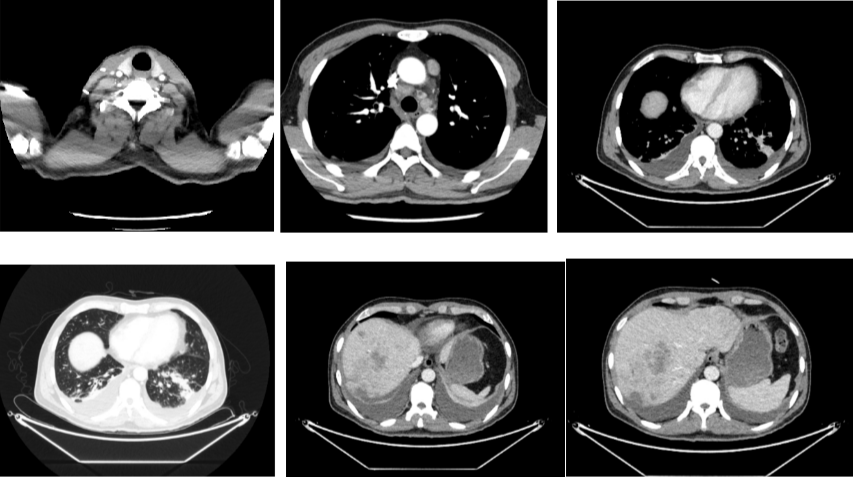

外院CT检查提示:1、两肺多发斑片状、结节影,性质待定,转移瘤?2、纵隔内多发肿大淋巴结;3、肝实质多发稍低密度影,性质待定(转移瘤可能性大)

2018-03-08 PET/CT示:胃癌(?)并全身多发淋巴结转移、肝脏多发转移、双肺上叶多发转移;

△2018-3-19基线CT

2018-11-14 CT(8周期化疗后):PD?

△基线水平

△治疗后

2020年4月复查:持续PR

增强CT示:肝硬化

肝异常强化灶

胃癌并肝转移化疗后,肝内转移灶大致同期;

右肺中叶外侧段、左肺上叶下舌段及右肺下叶后基底段慢性炎症;

右肺上叶前段实性微小结节,炎性结节?建议定期复查;

纵隔淋巴结转移瘤,复查大致同前。